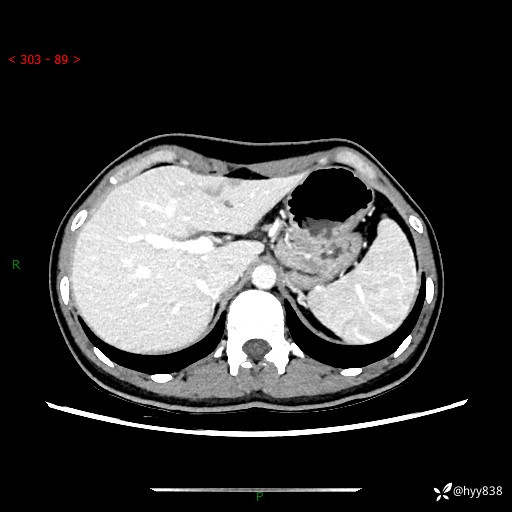

性别:女

年龄:23岁

简要病史:外院发现肝结节,来我院进一步增强确诊

上腹部CT平扫+增强

肝囊肿 (68)